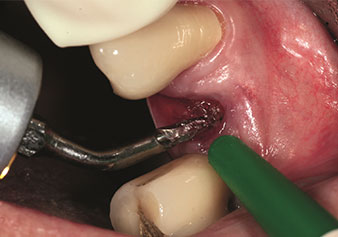

Sıklıkla hafife alınan uygulamalardan biri, alveolar yönetimin bir parçası olarak diş köklerinin veya kök parçalarının nazikçe çıkarılmasıdır. Şu anda iki modeli (W&H'ten EX1 ve EX2) mevcut olan hassas periotomlarla, özel olarak endodontik ön işleme tabi tutulmuş dişler veya ankilozik kökler de kolayca çıkarılabilir. Sonuç, sert ve yumuşak dokuları tamamen sağlam olan ekstraksiyon alveolleridir, çünkü genellikle onları açmak gerekli değildir.

Bu, daha sonra veya hemen implant bakımı için optimum bir temel oluşturur [şekil 1 ve 2, Dr. Torsten Conrad’ın (Bingen a. Rhein) onayı ile kullanılmıştır].

Hassas periotom (uç EX1)

Şekil 1: Hassas periotom (uç EX1).

Fotoğraf: © Dr Torsten Conrad (Bingen a. Rhein)